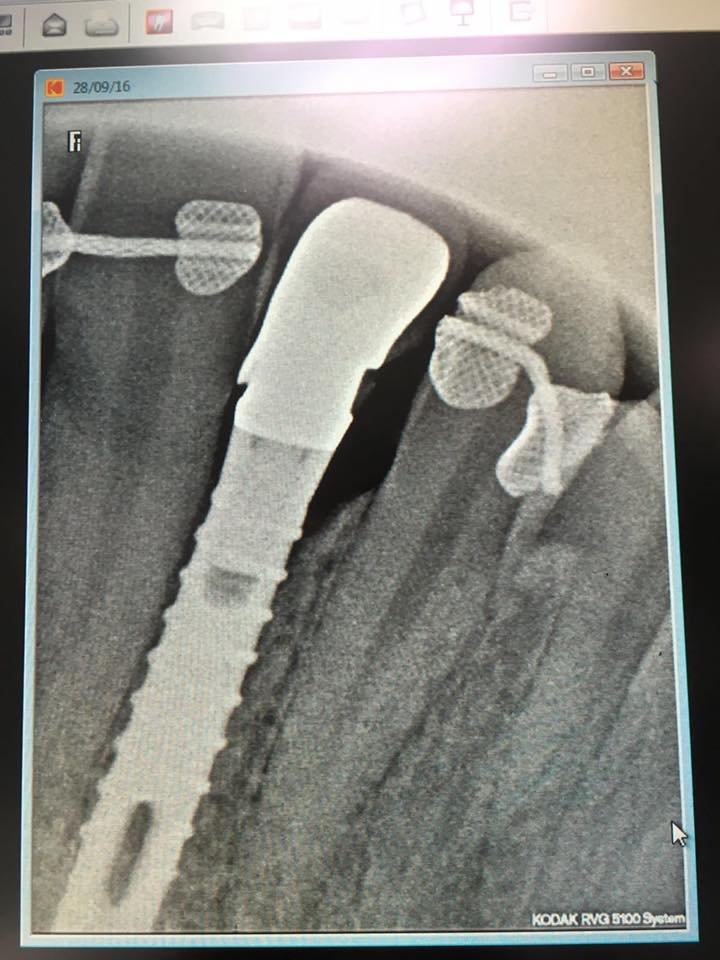

Buenos días, Aquí os dejo una Rx de un implante mundialmente conocido en nuestro grupo de Facebook. A ver que opináis.

Buenas noches, Ha acudido este paciente a consulta con la porcelana de la corona sobre implante fracturada. Me gustaría saber por favor, que marca de implante es para conseguir el [...]